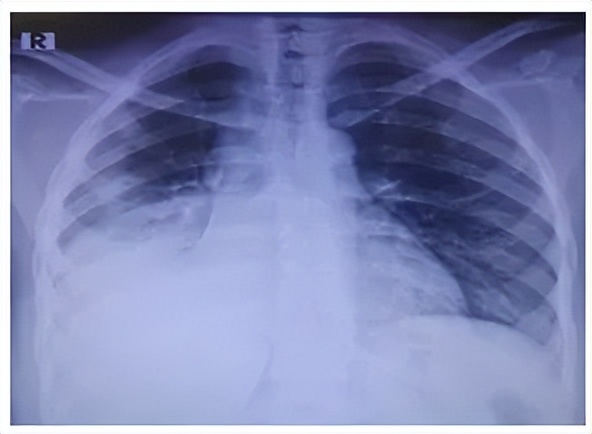

胸部X线:右肺中下叶均匀致密阴影,伴有胸腔积液及下方塌陷。